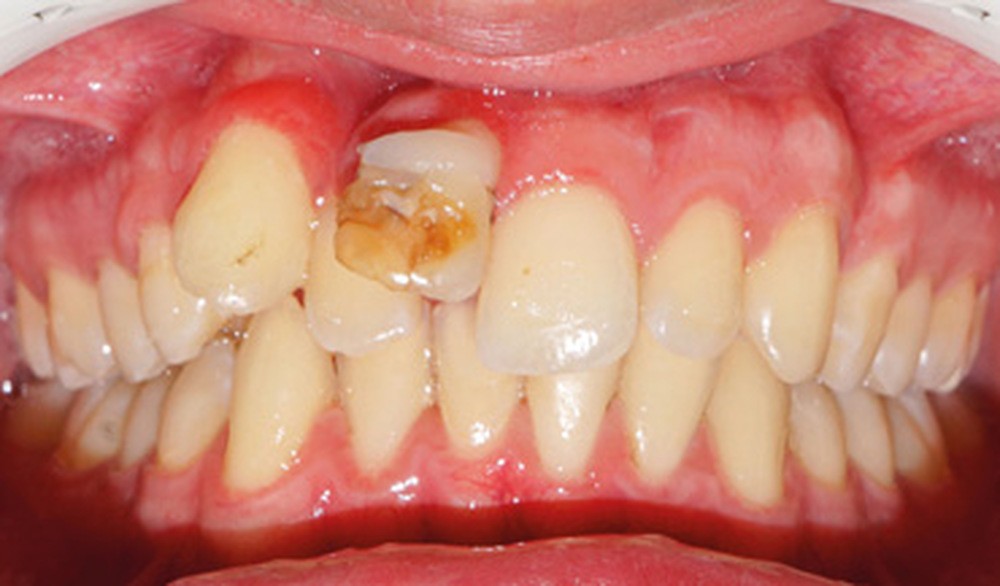

Son incisive centrale supérieure droite (11) présente un défaut de structure amélaire sévère, compromettant une technique restaurative pérenne a minima. L’examen de la panoramique (fig. 1e) et de la radiographie rétroalvéolaire de 11 (fig. 1f) objective une fracture coronaire verticale, ainsi qu’une racine grêle et courbe, peut-être en rapport avec un ancien traumatisme [1]. Le rapport couronne clinique/racine clinique est défavorable.

La concertation avec le chirurgien-dentiste traitant du patient nous a orientés vers la troisième option, la pérennité de 11 étant compromise sur le long terme et la morphologie radiculaire de 12 favorable à la substitution. De plus, elle assure une correction efficace de la classe II occlusale, tout en permettant un repositionnement incisif mandibulaire.